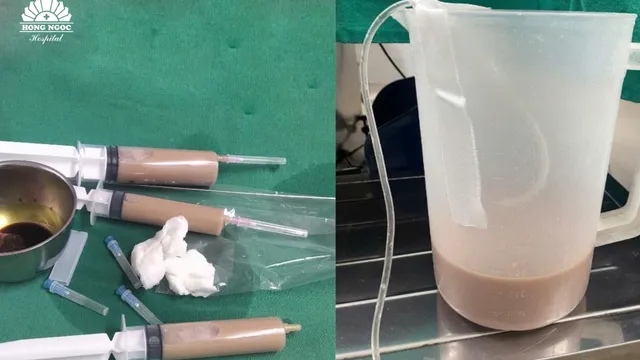

Bác sĩ tiếp tục chỉ định bệnh nhân chụp cộng hưởng từ (MRI) sọ não tìm căn nguyên gây bệnh, hình ảnh phát hiện khối vùng góc cầu tiểu não - lỗ tai trong trái dọc theo đường đi của dây thần kinh số 8, kích thước khoảng 9x4mm. Sau khi hội chẩn kỹ lưỡng, bác sĩ kết luận nguyên nhân chính xác gây tình trạng ù tai, nghe kém của bệnh nhân do khối u tại dây thần kinh số 8 gây ra.